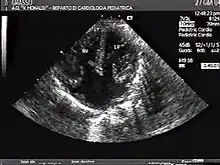

The proper development of the atrioventricular canal into its prospective components (The heart septum and associated valves) to create a clear division between the four compartments of the heart and ensure proper blood movement through the heart, are essential for proper heart function. When this process does not happen correctly, a child will develop atrioventricular canal defect which occurs in 2 out of every 10,000 births.[1] It also has a correlation with Down syndrome because 20% of children with Down syndrome have atrioventricular canal disease as well. This is a very serious condition and surgery is necessary within the first six months of life for a child.[2] Half of the children who are untreated with this condition die during their first year due to heart failure or pneumonia.[3]

Atrioventricular canal defect may be divided into partial or complete forms. In the partial form, openings between the left and right atria and improper formation of the mitral valve exist. In the complete form, there is free movement in all chambers because there is a large hole where the atria and ventricles meet, and instead of there being two valves there is one common valve.[4]